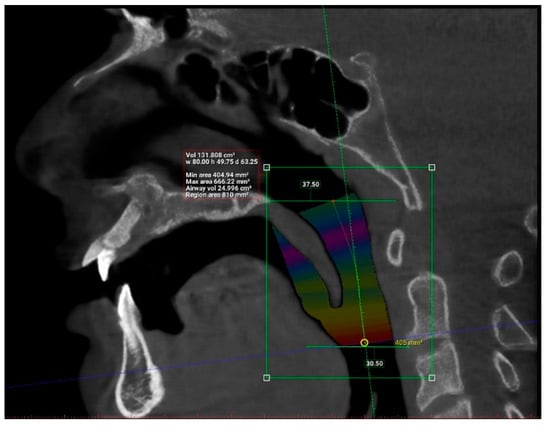

| N | Minimum | Maximum | Mean | Std. Deviation | |

| Length (mm) | 101 | 29.93 | 55.75 | 42.63 | 6.24 |

| Total volume (cm3) | 101 | 94.58 | 173.45 | 131.67 | 17.91 |

| Average volume (cm3) | 101 | 3.34 | 32.09 | 11.10 | 5.21 |

| Antero-posterior (mm) | 101 | 1.00 | 14.50 | 6.44 | 3.19 |

| Width (mm) | 101 | 8.00 | 37.00 | 21.69 | 6.54 |

| Valid N (listwise) | 101 |